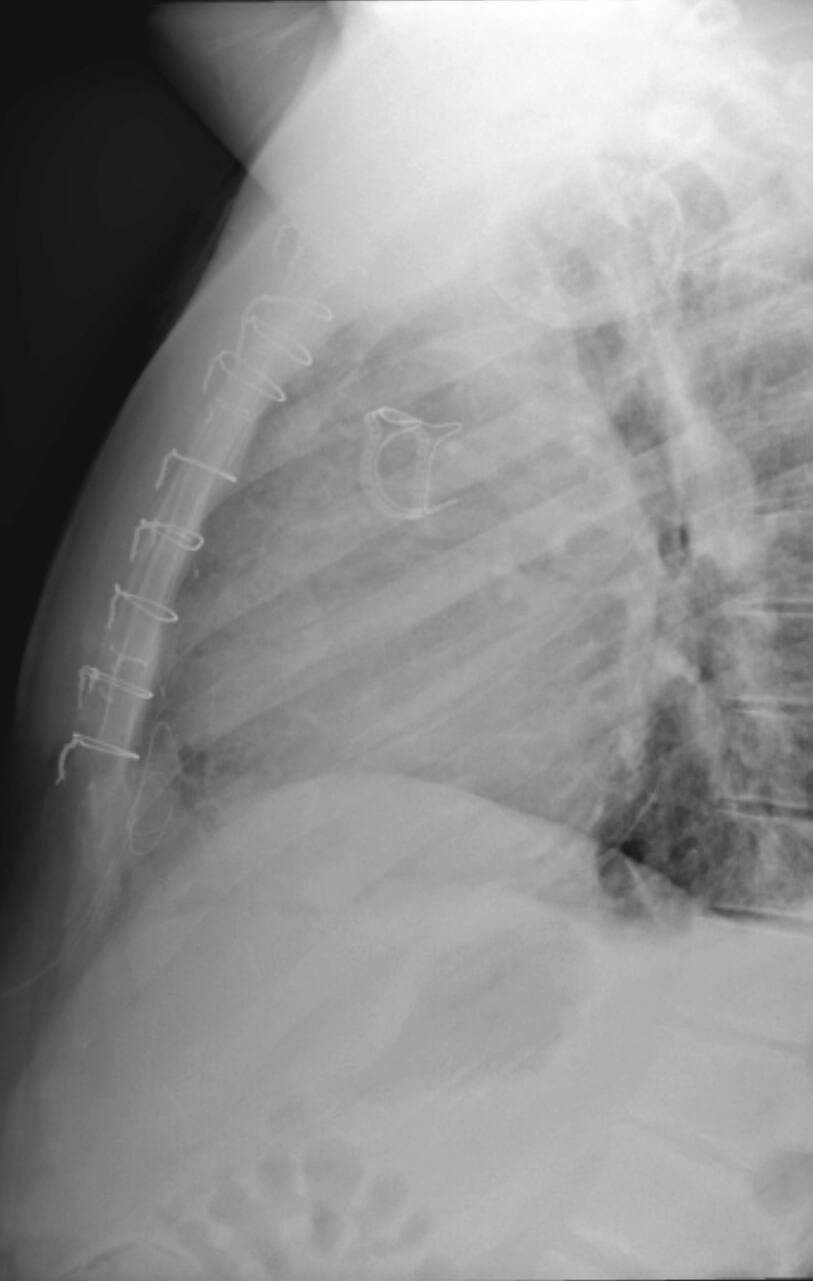

Elle est causée par deux drains d’une douzaine de pouces plantés dans mon ventre.

Qu’adviendrait-il de moi si je contractais le virus, alors que mon système immunitaire est à son plus bas ? Je n’ose même pas l’imaginer. L’idée de tousser à répétition m’effraie. Ce serait un véritable calvaire pour mon sternum « broché ».